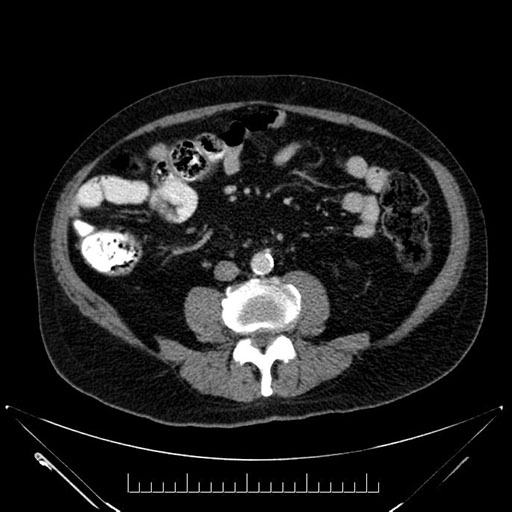

Whipple (pancreaticoduodenectomy) [case 7]

Imaging Analysis

Look through the patient's CT scan to identify any areas of concern for the necessary procedure.

Axial - stented